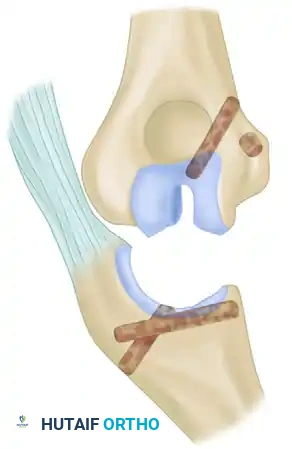

3. Ligament Reconstruction (The Arafiles Technique)

In cases of profound instability where dynamic fixation is unavailable or insufficient, surgeons may opt for ligament reconstruction with or without adjunctive fixation. The Arafiles technique utilizes a tendon graft routed through precisely drilled osseous tunnels to recreate the stabilizing vectors of the collateral ligaments.

The following sequence illustrates the complex reconstruction for an old posterior dislocation of the elbow, demonstrating the slot created in the trochlea and the specific lines of drill holes (A to D) that dictate the course of the tendon graft.

Note the intact forearm flexor origin during the completed repair, which provides secondary dynamic stability to the medial aspect of the reconstructed joint.